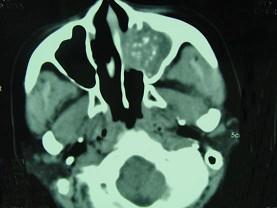

问题 男,41岁,左侧鼻腔胀痛半年余,CT检查如图,最可能诊断为 ( )

选项 A、真菌性鼻窦炎 B、上颌窦癌 C、化脓性鼻窦炎 D、变应性鼻窦炎 E、出血坏死性息肉

答案 A